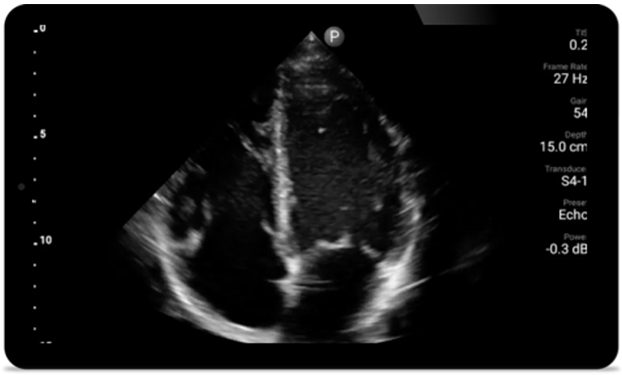

Cada segundo cuenta en la atención cardíaca

Los pacientes que sufren un ataque cardíaco necesitan atención inmediata. Los ajustes cardíacos preestablecidos de Lumify pueden ayudar a los pacientes a ser diagnosticados más rápido para mejorar sus resultados.

• Rango extendido de frecuencias de operación de 4 a 1 MHz • 2D, Doppler a color, Modalidad M, XRES avanzado e imágenes armónicas multivariables • Imágenes de alta resolución para aplicaciones abdominales y cardíacas: las optimizaciones de preajustes de imágenes cardíacas, gineco-obstétricas, pulmonares, abdominales y FAST de Lumify ayudan a la tecnología que salva vidas en entornos prehospitalarios